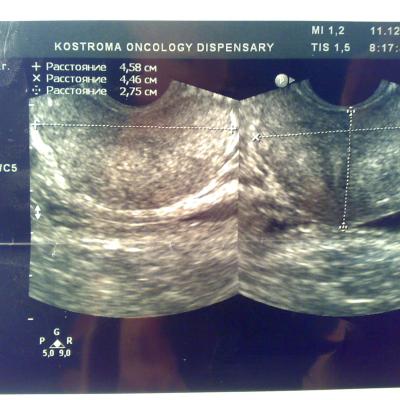

Посмотрите пожалуйста снимки узи, какие выводы можно сделать кроме увелечинных размеров? Может ли это влиять на эректильную функцию или изменение гормонального статуса? Болевых ощущений нет, есть небольшой дискомфорт, мочеиспускание в норме, но струя послабже чем была.Очень переживаю, ночами не сплю из-за нервов, без седативных уже и не уснуть.Заранее благодарен.

Ваши симтомы не связаны с предстательной железой. Вам нужен хороший психолог или психоаналитик. Уролог не нужен.